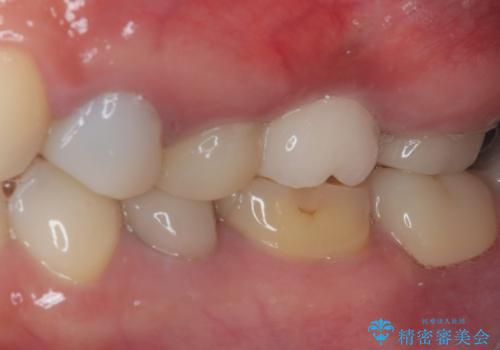

- 奥歯のクラウンが土台ごと外れてしまったとのことで来院された患者様です。

保存可能ではありましたが、予後不良と患者様ご自身が判断されており、相談の結果抜歯即時埋入インプラントによる補綴治療を行うこととしました。